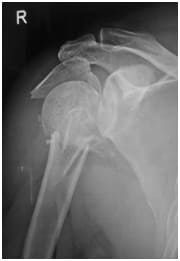

Very bad fracture with Many parts

Complex Shoulder FracturesShoulder Fractures are extremely common and while a lot of them are ‘simple’ and do not require surgery, if the fracture is displaced sufficiently, or if there are more “ parts”, then these fractures do need an operation.